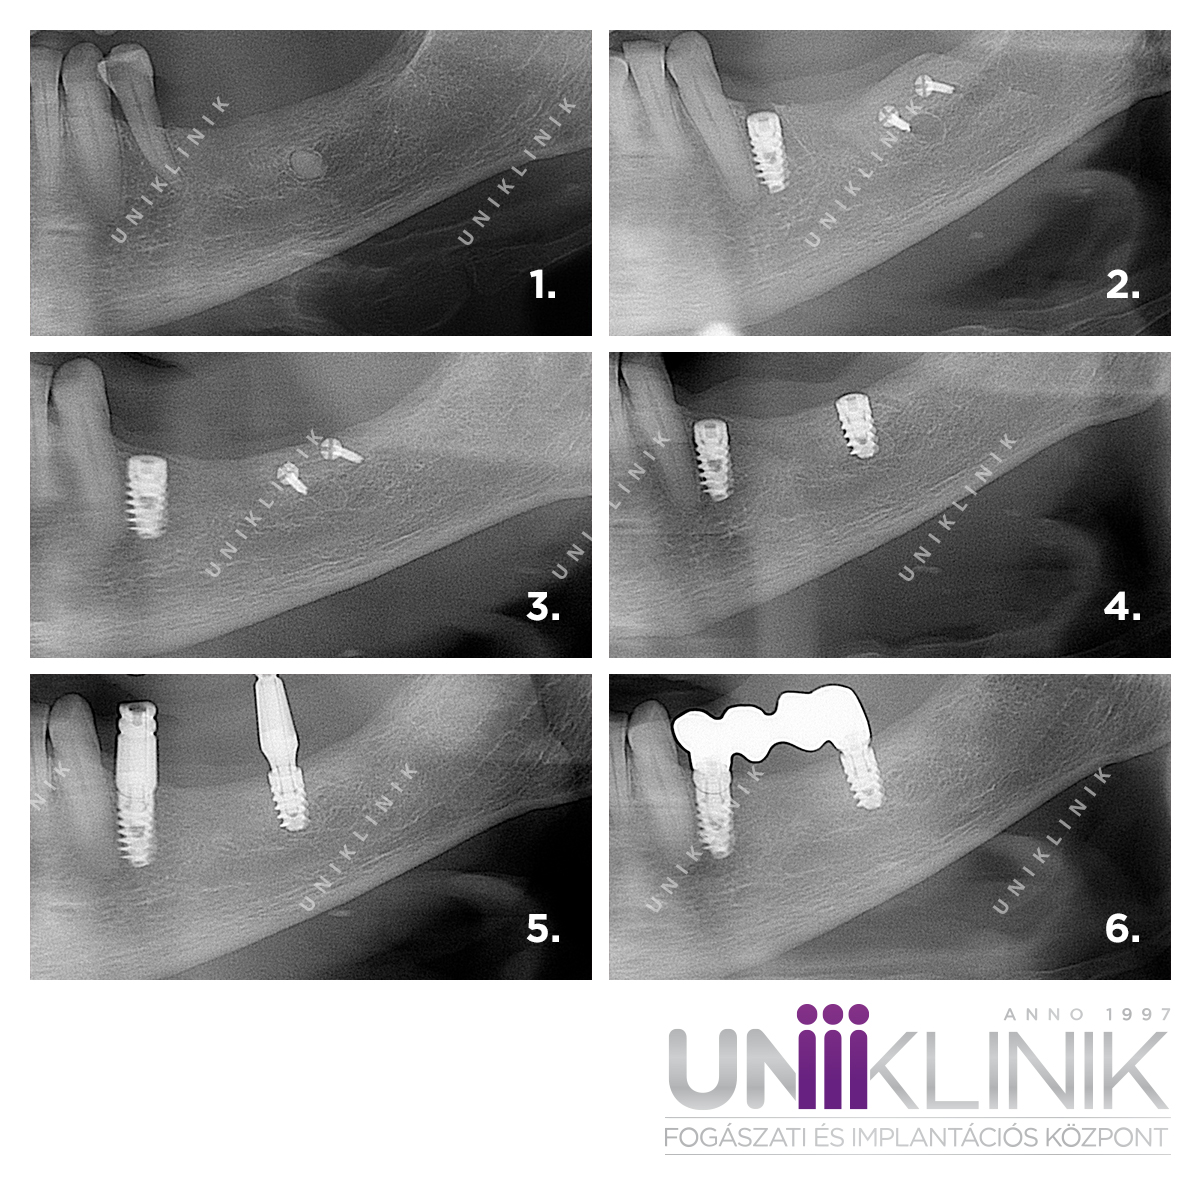

The following collage shows images of a bone block surgery performed in a case of significant bone loss. During the bone grafting procedure, Dr. Balázs Záhonyi, a dentoalveolar oral surgeon, transplanted a bone block from the posterior jaw area to the site where the implant was to be placed. The bone block was secured with titanium screws.

After the bone block surgery, a healing period of 3-6 months is required for the bone to integrate. Following this, the dental implant can be placed in the augmented area, and after an additional 4-6 months of healing, the final restoration can be made. In this case, the final restoration was a three-unit dental bridge supported by two implants.